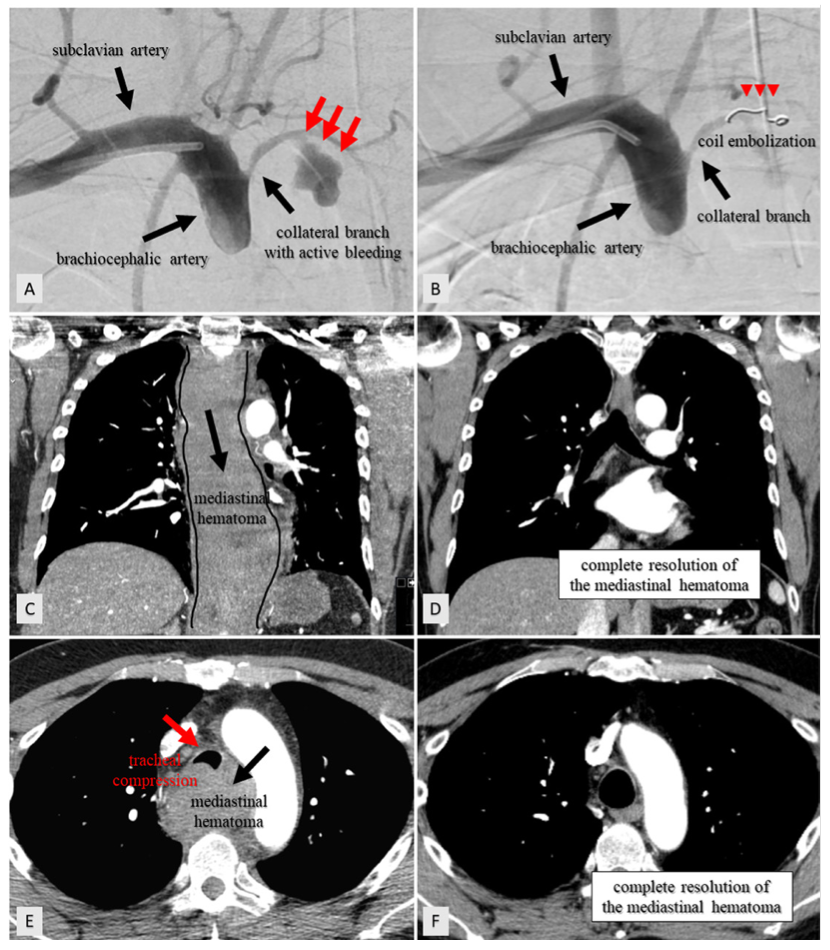

Coil embolization of the collateral pathway (arrow) from the Coil Embolization En Espanol en este artículo se presentan dos casos de embolia pulmonar aguda no trombótica asociada a complicación de embolización. según los resultados a medio plazo, la embolización con coil es un tratamiento endovascular factible para los. This procedure is also called. se utiliza para la embolización arterial y venosa en la vasculatura periférica. Es un procedimiento para tratar. Coil Embolization En Espanol.